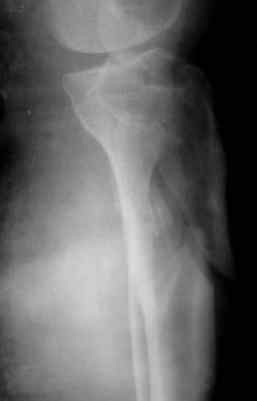

Уважаемые коллеги, случай интересен прежде всего тем, что в данном переломе присутствуют два компонента - внутрисуставной и метадиафизарный, требующих соблюдения разных принципов при хирургическом лечении. Для внутрисуставного компонента необходима анатомичная репозиция с межфрагментарной компрессией и достижением абсолютной стабильности. При наличии импрессии надо быть готовым к замещению дефекта. Артротомию выполнять придётся, но она может быть достаточно деликатной, что, впрочем, не всегда возможно. И здесь хорошим подспорьем является предварительно наложенный аппарат внешней фиксации. Для артроскопически ассоциированной репозиции всё-таки лучше подходят случаи с преобладанием импрессии, а не раскалывания, как у данного пациента.

Для метадиафизарной части этого повреждения обнажение перелома с анатомичной репозицией не является абсолютно необходимым, и, более того, неизбежно приведёт к деваскуляризации кости и возможным проблемам с заживлением перелома. Для этой части перелома желательно шинирование без обнажения зоны перелома. Шинирование может быть интрамедуллярным соответствующим гвоздём или экстрамедуллярным (пластиной или аппаратом внешней фиксации). Главное для метадиафизарной части перелома - это восстановление длины, оси конечности с правильной ротационной установкой и достижением относительной стабильности.

В заключение - клинический пример хирургического лечения похожего перелома из моего архива (1,2). После анатомичной репозиции суставной поверхности с введением стягивающего винта замещён дефект (3,4). Метадиафизарная часть перелома шинирована блокированной пластиной без обнажения отломков (5,6,7).